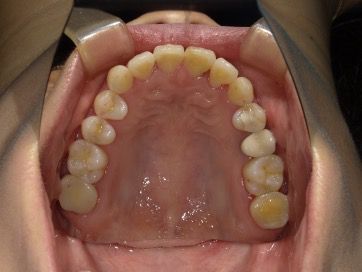

30代 女性 叢生

BEFORE

30代 女性 叢生 BEFORE

• 上下に叢生が見られる。歯列の拡大、臼歯の遠心移動、IPRを組み合わせてインビザラインで治療を行う事にした。

• 下顎前歯が1本欠損しているので、上顎の正中と下顎の正中はずれてしまう。

• コンプライアンスが良く、治療に協力的だったため治療はスムーズに進んだ。

30代 女性 叢生 術前上

30代 女性 叢生 術前下